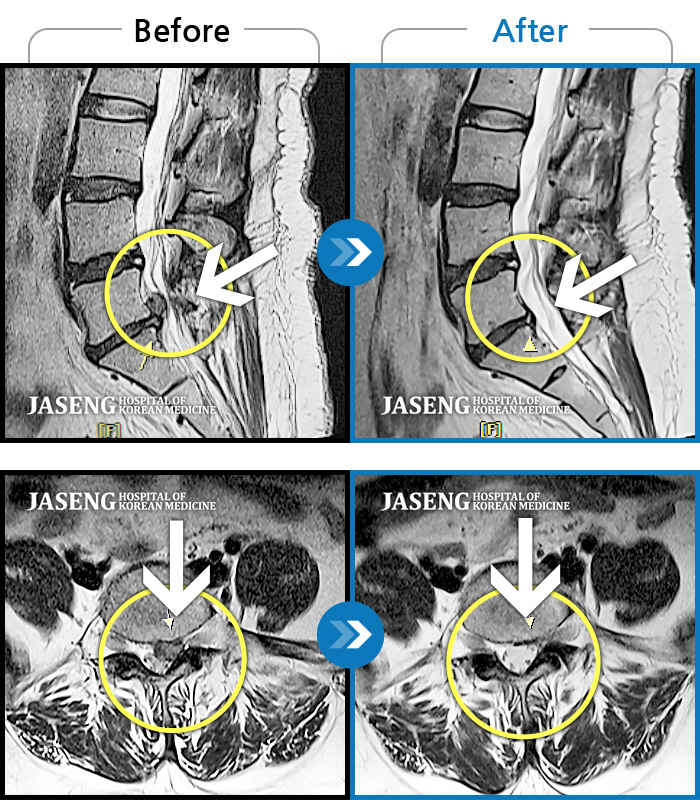

Before

After

환자에게 사전 동의를 받아 동일 조건에서 촬영되었습니다.

개인에 따라 치료 후 부작용이 발생할 수 있으니 의료진과 상담 후 치료를 진행하시기 바랍니다.

허리 우측에서 발바닥까지 통증, 누워있을 때 당기는 증상

허리통증과 좌측 엉덩이에서 다리까지 방사통, 야간통